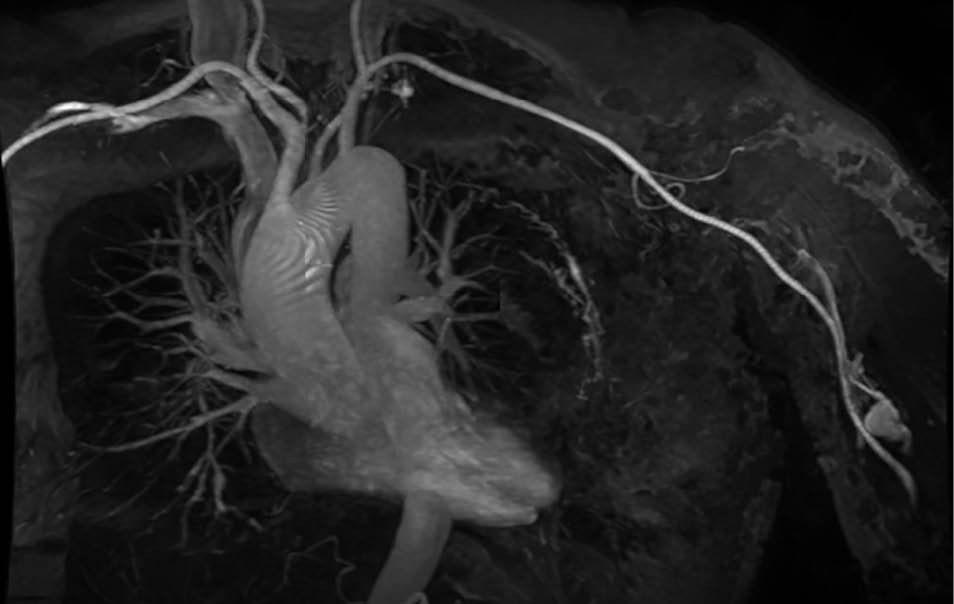

Aufgrund der symptomatischen Cholezystolithiasis nach stattgehabter akuter Cholezystitis wurde die Indikation zur elektiven laparoskopischen Cholezystektomie gestellt. An diagnostischen Verfahren wurden auswärts ein Angio-MRT (Abb. 1 – 4) des Oberbauches und eine Magnetresonanz-Cholangiopankreatikographie (MRCP) durchgeführt, welche eine Cholezystitis bei Cholezystolithiasis und eine beginnende Leberzirrhose nachweisen konnten. Im Rahmen der präoperativen Vorbereitung wurde eine Echokardiographie durchgeführt, in welchem eine Herzinsuffizienz infolge der Volumenbelastung durch die AV-Shunts i.R. des KMS und eine „Cirrhose cardiaque“ ausgeschlossen werden konnten. Als Marker einer intravasalen Gerinnungsaktivierung wurden erhöhte Prothrombinfragmente, D-Dimere und eine erniedrigte Antiplasmin-Konzentration sowie eine gesteigerte Fibrinolysekapazität detektiert. Eine sekundäre Thrombozytopenie oder eine Fibrinogen- und Faktor-XIII-Verminderung konnten ebenso wie das Vorliegen eines erworbenen von-Willebrand-Syndroms ausgeschlossen werden.

In einer hämostaseologischen Vorstellung wurde die Pausierung der Thrombozytenaggregationshemmung über 7 d unter „Bridging“ mittels niedermolekularem Heparin und eine medikamentöse Hemmung der Hyperfibrinolyse durch Tranexamsäure bis zum 3. postoperativen Tag bzw. in Abhängigkeit von Klinik und des hämostaseologischen perioperativen Monitorings empfohlen. Als perioperative Antibiotikaprophylaxe wurde Imipenem eingesetzt. Der Kameratrokar wurde entsprechend der aus dem Angio-MRT bekannten linksseitigen Ausprägung der Gefäßmalformationen (Abb. 1 – 4) in typischer Nabelposition platziert.

Abb. 1: Angio-MRT mit Transversalschnitt des oberen Abdomens auf Höhe der Gallenblase: Neben der hydroptisch geschwollenen und wandverdickten Gallenblase -> Hämangioendotheliom

im Bereich der ventralen und dorsalen linken Rumpfwand

Abb. 4: MR-Angiografie

(koronare Projektion) – betonte Intercostalarterien